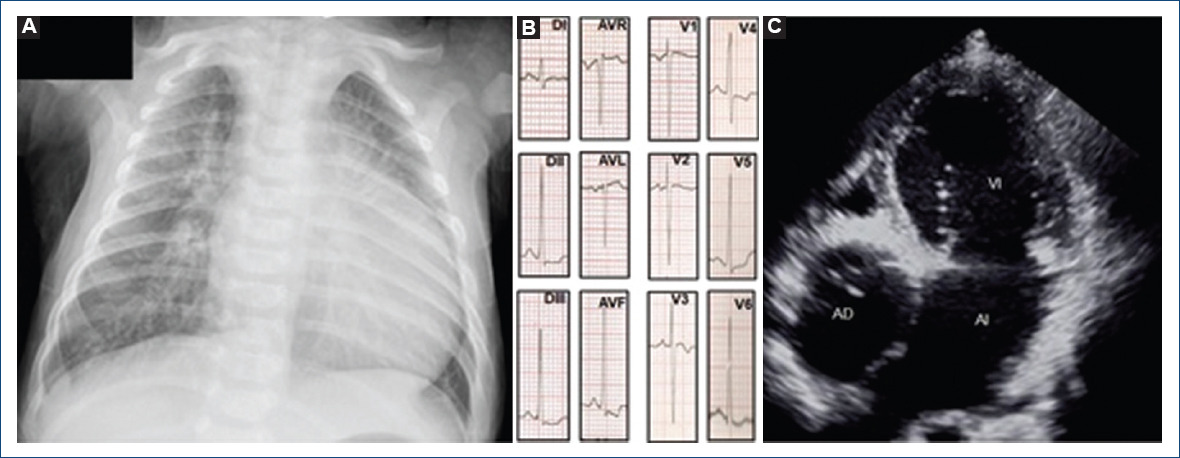

We present the case of a 4-year-old male patient with a history of dyspnea and diaphoresis since the age of 2 months. The physical examination showed respiratory distress, left parasternal regurgitant systolic murmur, single and intense second sound, hepatomegaly, and wide pulses. The X-ray with cardiomegaly and increased pulmonary blood flow. The electrocardiogram showed sinus rhythm, left ventricular hypertrophy, and decreased J point in V5-V6. Echocardiography and tomography diagnosed absence of the right atrioventricular connection with wide atrial septal defect, restrictive ventricular septal defect, ventriculoarterial discordance, interruption of the aortic arch type A, and a non-restrictive, 3 x 4 mm patent ductus arteriosus with the right-to-left shunt, which translates suprasystemic pulmonary pressure (Fig. 1). He was taken to correction of aortic arch interruption with end-to-end anastomosis, atrioseptectomy, and DKS with a 5 mm systemic-pulmonary shunt, with adequate postoperative evolution without post-surgical pulmonary hypertension, and discharged 3 weeks after (Fig. 2). This extremely rare association of congenital heart disease treated with DKS, to our knowledge, has been reported in less than 10 times in the literature2,3,6-8. Despite the complexity in the management, he has remained stable in the 2-year follow-up with good quality of life.

Figure 1 A: x-ray with cardiomegaly at the expense of the left cavities and increased pulmonary blood flow. B: electrocardiogram: Sinus rhythm, rS pattern in V1 and V2, left ventricular hypertrophy and left ventricular diastolic overload. C: echocardiogram: apical four-chamber image showing absence of the right AV connection.